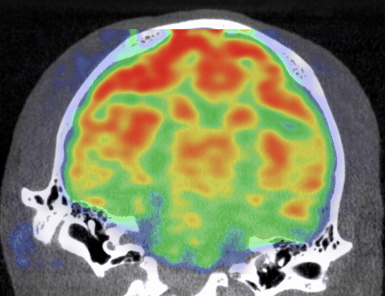

CASE 5: NHP brain PET/CT dynamic MPPF imaging

workimg

• Courtesy of: CERMEP, Lyon, France

Research objective: Investigation of MPPF uptake in NHP brain

Animal model: NHP, ~ 3 kg

Acquisition protocol: PET imaging: 90 min acquisition, injection right after acquisition starts. CT imaging: 80kV, 40s

Processing and reconstruction protocol: PET: 3D OSEM, 9x 10 min, 0.84 mm isotropic voxel size. CT: 0.15 mm isotropic voxel size

Biomarker or contrast agent: 18F-MPPF, ~ 3 mCi